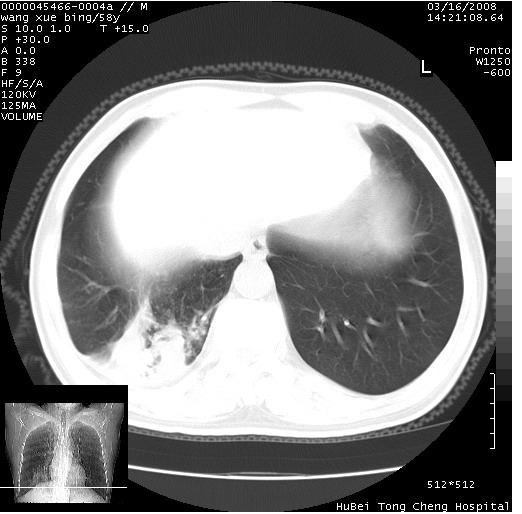

患者 男,58岁。咳嗽、咯血3月余。

胸部cr x线片提示:1)右下肺脓肿。2)右下肺周围型肺癌不排除。建议:行ct扫描检查。

胸部ct轴位平扫(层厚10mm,螺距1.5,重建间隔10mm),图像如下:

右肺下叶团块及不规则空洞,内壁不规则,外缘见粗长毛刺,临近胸膜明显增厚并与病灶关系密切。支持考虑:右肺肺脓肿!建议穿刺病理检查待除外周围型肺癌!

右肺下叶见不规则厚壁空洞,内壁不规则,外缘见粗长毛刺,临近胸膜明显增厚并与病灶关系密切。支持考虑:周围型肺癌!

右肺下叶周围型肺癌伴空洞形成!征象比较明显!分叶、毛刺、胸膜凹陷征、厚壁空洞,壁结节!

空洞壁厚,不规则,其内可见壁结节,周围可见毛刺及阻塞性炎变,多考虑癌性病变.

空洞内壁不规整,有壁结节,周围有毛刺,支持癌性空洞。